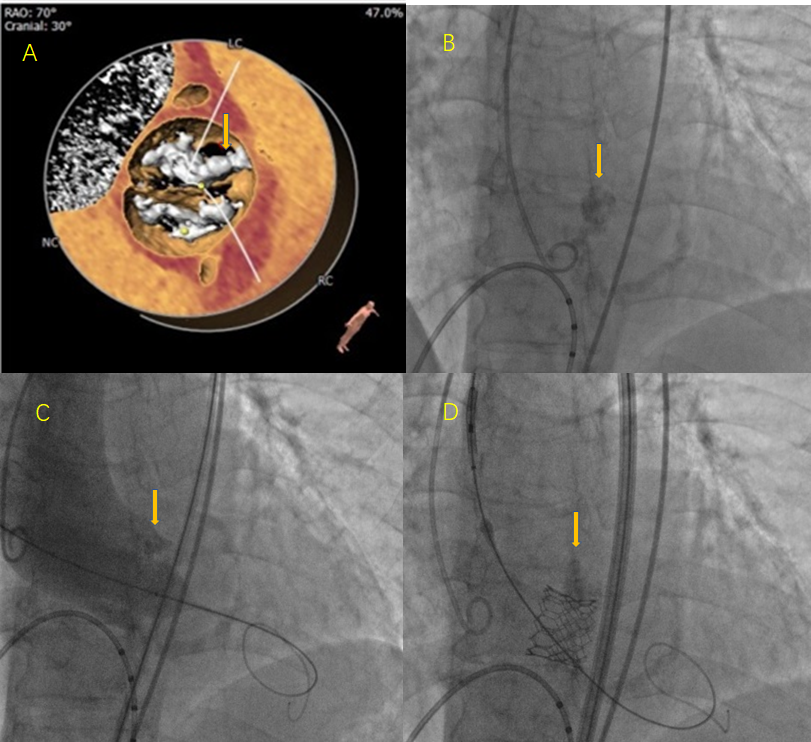

TYPE0型二叶式主动脉瓣,瓣叶严重钙化增厚。冠脉无明显狭窄,冠脉开口高度左侧15.4mm、右侧14.9mm,冠状窦水平无瓣叶,TAVR手术冠脉闭塞风险低。升主动脉扩张,主动脉扭曲。双侧股动脉通畅,无明显钙化。

二叶瓣严重钙化(如图A、B 所示术前CT检查及术中影像均可见明显钙化团块),术中发生瓣周漏、瓣膜移位、瓣环破裂等风险较高,TAVR操作具有一定挑战性。升主动脉明显增宽,再加上主动脉瓣钙化严重,为器械输送增加难度。

图A、B 术前CT检查及术中影像均可见明显钙化团块(箭头所示),图C、D:球囊预扩张及人工瓣膜植入过程中均可见钙化团块明显移位(箭头所示)。